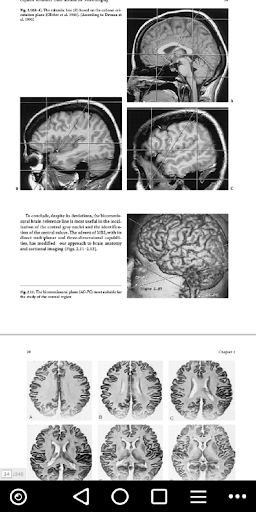

The App provides a unique review of the essential topographical anatomy of the brain from an MRI perspective, correlating high-quality anatomaical plates with the corresponding high-resolution MRI images. The App includes a historical review of brain mapping and an analysis of the essential reference planes used for the study of the human brain. Subsequent chapters provide a detailed review of the sulcal and the gyral anatomy of the human cortex, guiding the reader through an interpretation of the individual brain atlas provided by high-resolution MRI. The relationship between brain structure and function is approached in a topograhical fashion with analysis of the necessary imaging methodology and displayed anatomy. The central, perisylvian, mesial temporal and occipital areas receive special attention. Imaging of the core brain structures is included. An extensive coronal atlas concludes the app. Neuroscientists, neuroradiologists, neurologists, neurosurgeons and students of human behavior should find this app useful guiding them to a better understanding of the localization of brain function.